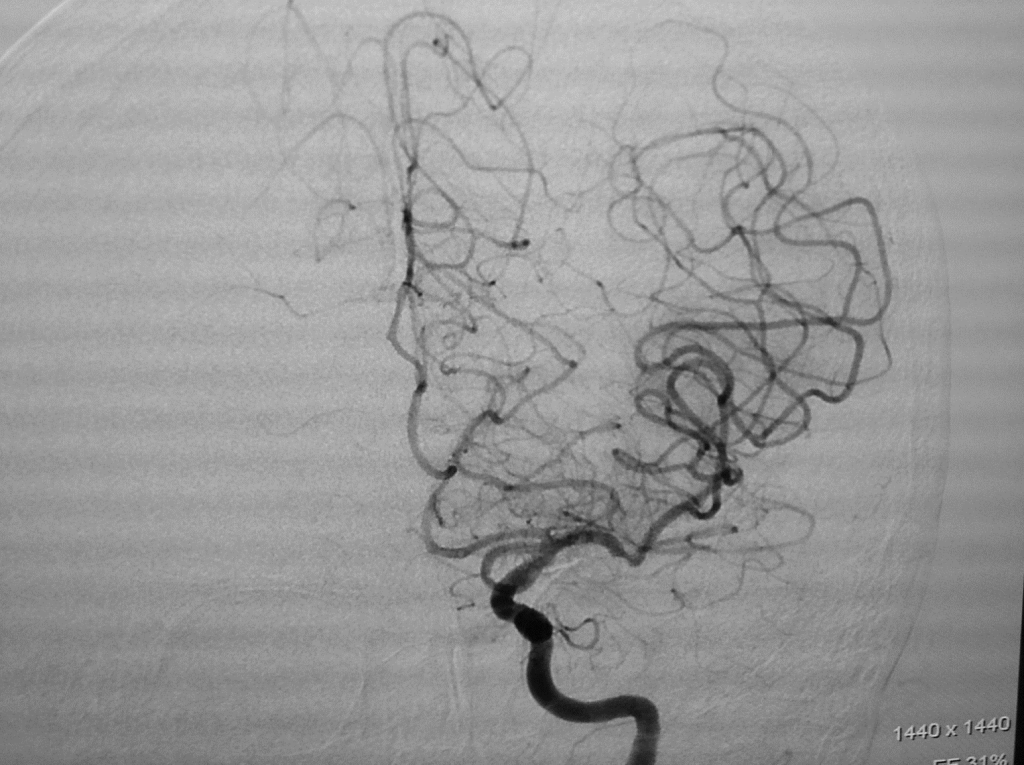

Red arrow point to blockage of middle cerebral artery.